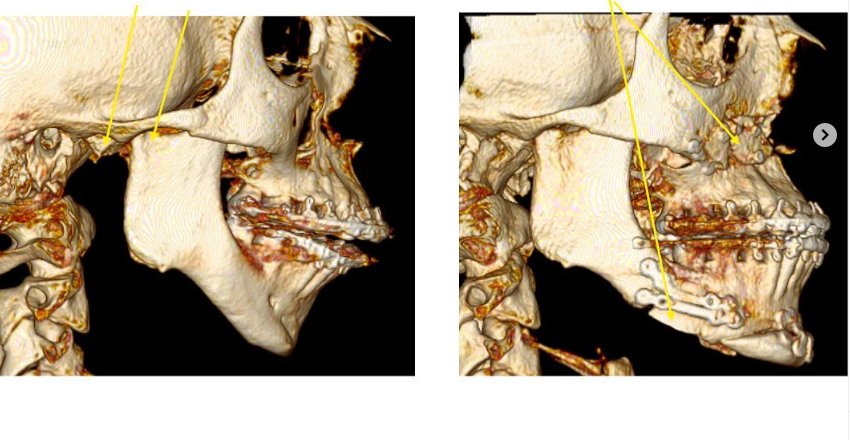

Lets be clear this is not hate, but doing bonegraft helps with not creating step offs and filling in gaps of leforts and bsso obv. Most of the time the gaps will be filled nonetheless to some degree but bone grafts is more of a guarntee. Also alfaro has many patients i have been in contact with where the bone didnt get healed fully because of huge movements and no bonegrafting and only anterior plates, ram does kinda the same except he dont do the same big movements.

And its more important if you do big bsso cuts, genios or maybe the most important one for big downgrafts of the maxilla.

look in the pic below for example at the cuts shown with red circle:

more no bonegraft huge genio from ram

huge movements from ram no bone graft

raffaini doing big bonegrafts

Also some people might say that bonegraft dont show in ct/cbct, it def does

look in the pic below for example at the cuts shown with red circle:

more no bonegraft huge genio from ram

huge movements from ram no bone graft

raffaini doing big bonegrafts